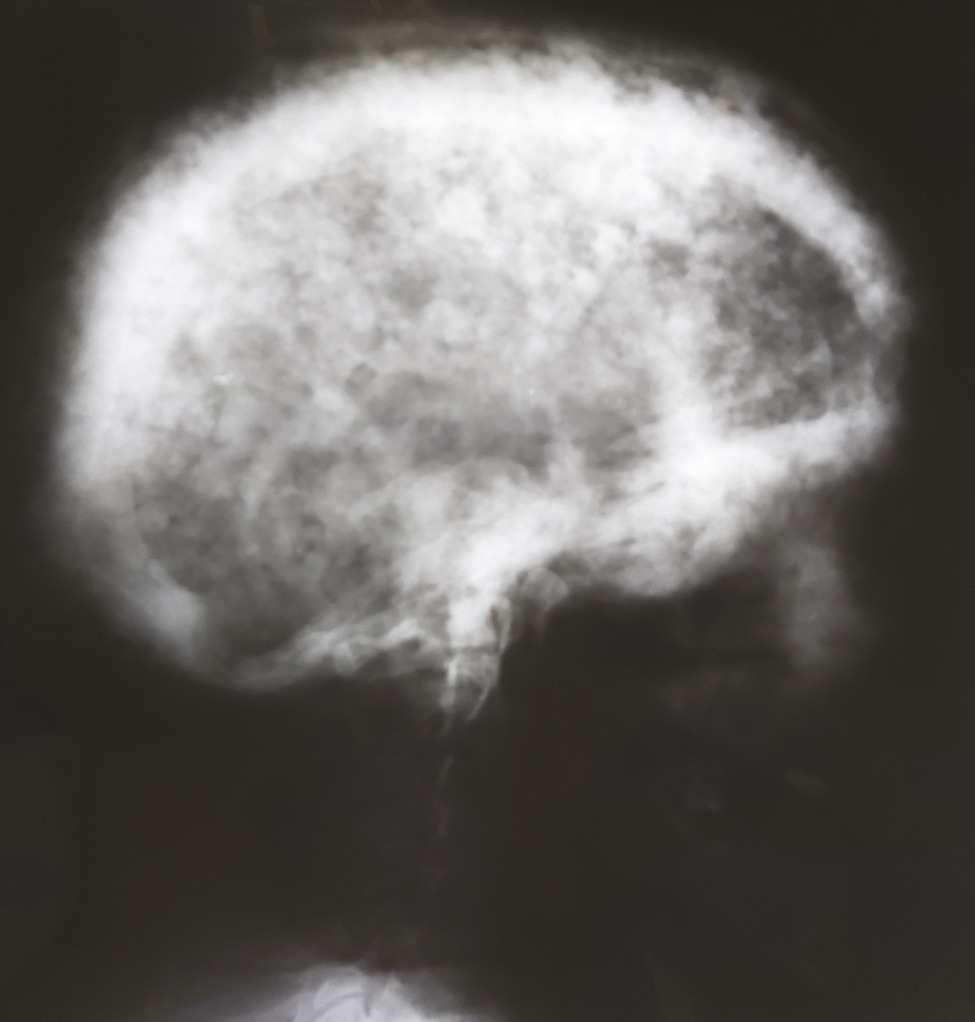

Un homme de 77 ans décrit des céphalées chroniques avec hypoacousie profonde. L’examen clinique constate une macrocrânie. La radiographie du crâne de profil montre un aspect cotonneux avec des lésions ostéocondensantes et lytiques (fig. 1). Les phosphatases alcalines sériques sont à 1 700 UI/L (13 fois la normale). Le taux de protéine C-réactive (CRP) est de 7 mg/L. La calcémie est à 91 mg/L. La scintigraphie osseuse met en évidence une hyperfixation intense du crâne, des mandibules, de l’aile iliaque gauche, de l’ischion gauche, du sacrum, de l’arc moyen de la 8e côte droite et de la 4e vertèbre lombaire (fig. 2). Ces anomalies sont typiques de la maladie osseuse de Paget. Un traitement par acide zolédronique a été initié, puis le patient a été perdu de vue.

La maladie osseuse de Paget est une ostéopathie bénigne. La majorité des patients sont asymptomatiques. Le diagnostic est souvent posé devant la découverte fortuite d’une augmentation inexpliquée des phosphatases alcalines sériques, ou lors d’un bilan radiologique réalisé pour un autre motif. L’aspect cotonneux du crâne est un signe radiographique caractéristique reflétant l’activité ostéoblastique et ostéolytique mixte. La scintigraphie osseuse permet de déterminer l’étendue et la localisation des lésions. L’augmentation des phosphatases alcalines sériques reflète l’activité et l’étendue de la maladie. Le traitement repose sur les bisphosphonates. La calcitonine, moins efficace, est une alternative thérapeutique de deuxième intention.1, 2